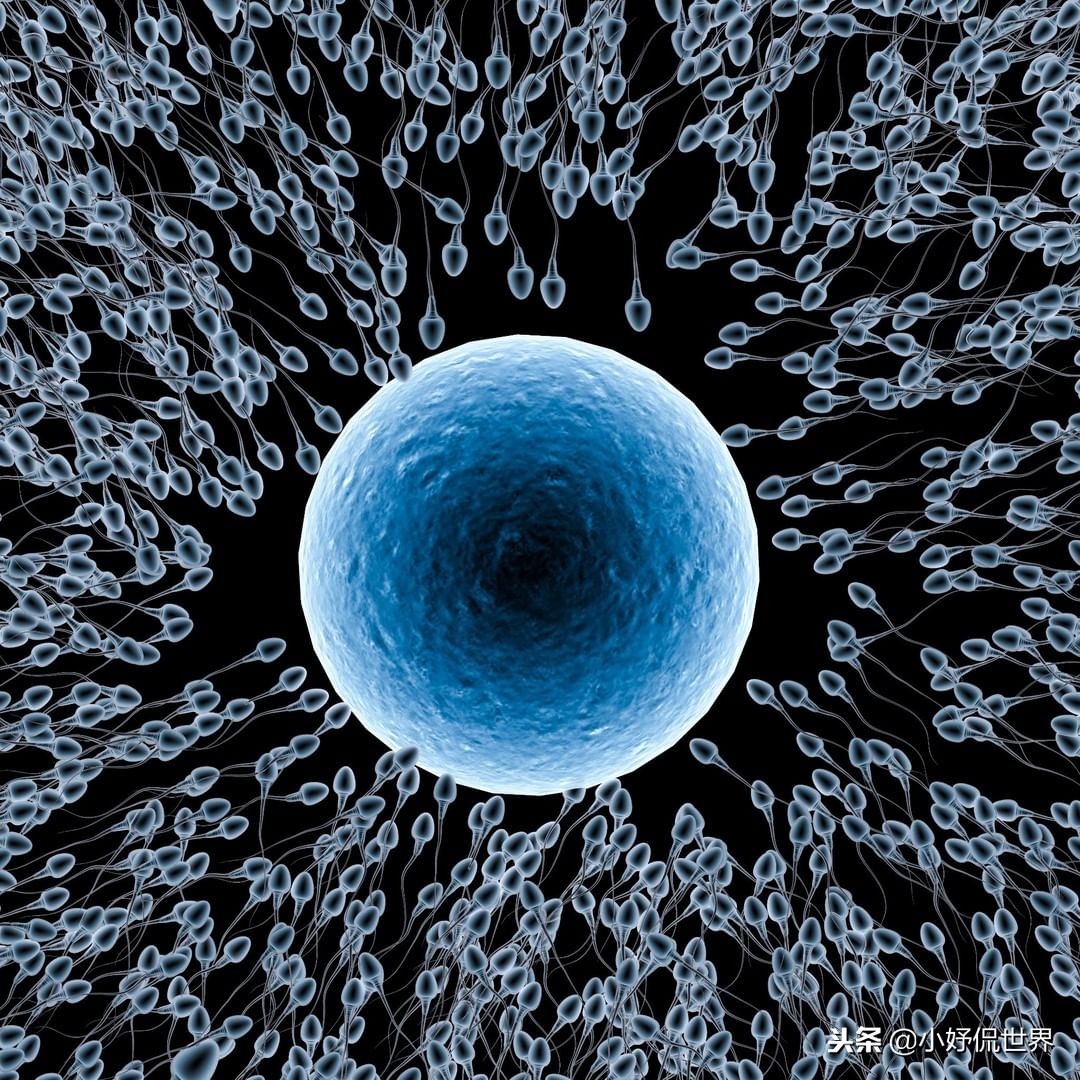

15、卵子和精子

生命的延续是个非常神奇的过程,我们在生物课上都学到过,经过卵子和精子结合的受精过程后,才出现了真正的新生命。而这张彩色的受精前的卵子被精子所包围的照片,则带给人更多的想象空间。